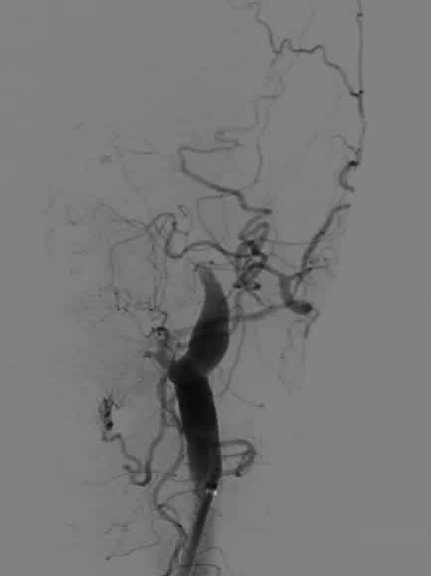

DSA显示ICAO

微导管造影证实MCAO

手术过程

中间导管配合在长鞘和小球囊的配合下穿过迂曲夹层的颈内动脉。

微导管微导丝越过MCA闭塞段,置入取栓支架支架。

微导管微导丝穿过夹层段,4.0×20mm球囊再次反复贴附夹层段,促进内膜贴壁。

造影观察,管腔狭窄较前好转,血流状态稳定,结束手术。